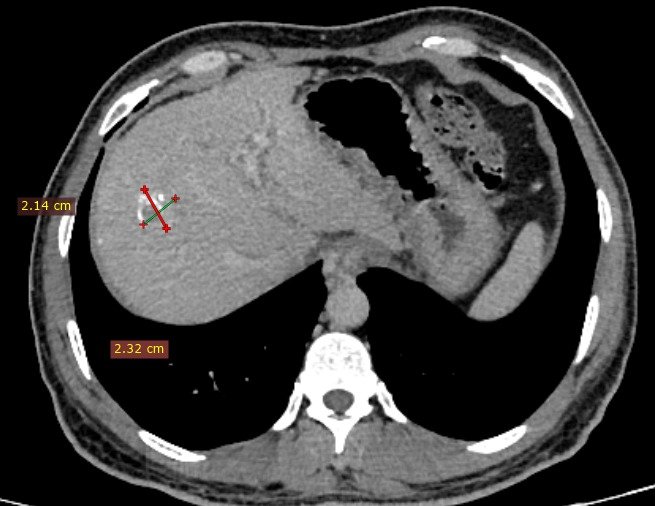

Minimally invasive treatment for liver cancers- TACE, Ablation and embolization

Tumor ablation, embolization , biopsy and FNAC. Palliation

Outcomes observed in patients treated with image-guided, minimally invasive vascular procedures.

Results vary by patient and condition. Images are for educational purposes only.